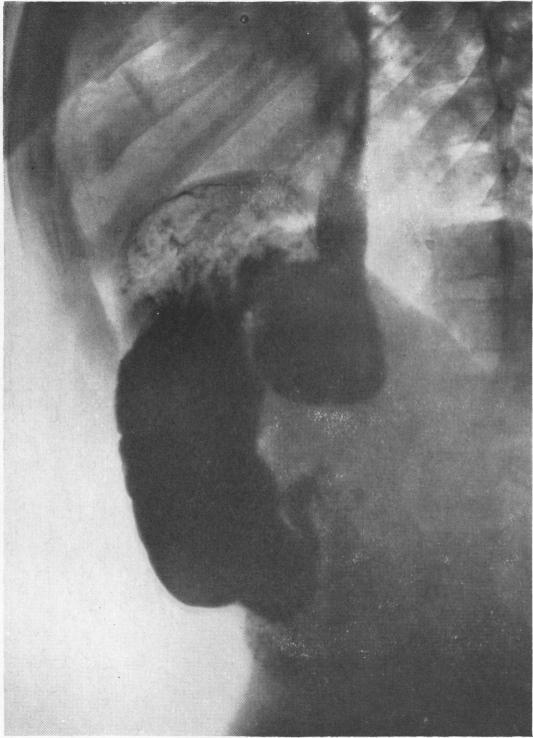

Fifty-seven cases of diaphragmatic hernia and eventration.

Thorax. 1950 Dec;5(4):343-61. doi: 10.1136/thx.5.4.343.